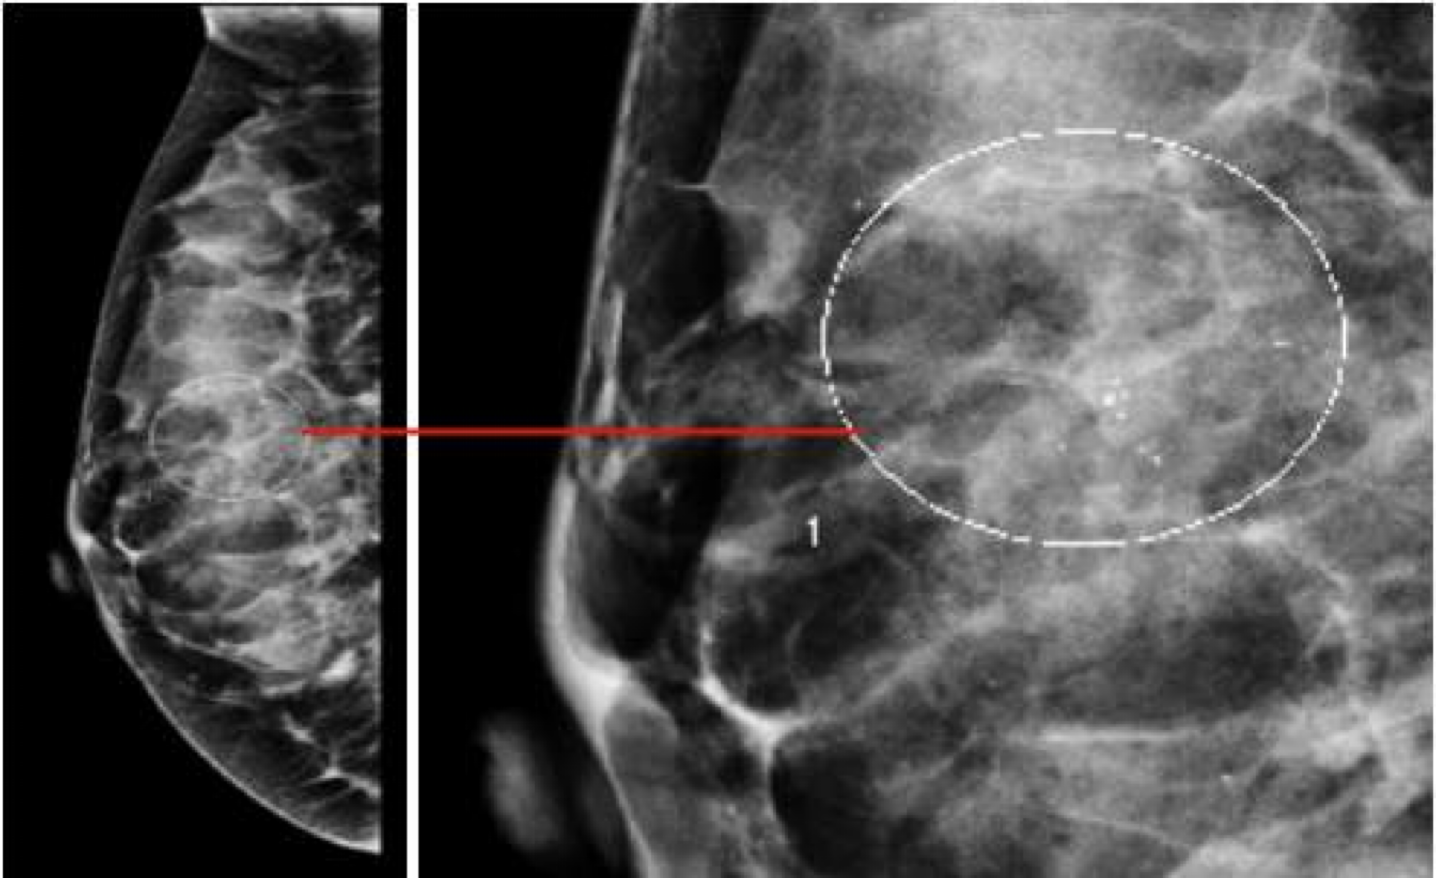

**A high-resolution x-ray taken in 2 views- medio-lateral oblique (MLO) & cranio-caudal (CC).

Abnormalities: architectural distortion, nodularity, mass, stellate lesion, microcalcifications, skin retraction, nipple changes and duct changes.

Additional views. Such as magnification views are done to detect microcalcifications

Mammography findings of benign and malignant breast lesions #Z

| Appearance of the lesion | - •Well-defined, circumscribed mass | - •Focal mass or density |

| Margins z | - •Surrounding radiolucent ring (halo sign) | - •Poorly defined, spiculated margins |

| Calcifications | - •Diffuse microcalcification or coarse calcification | - • Clustered microcalcifications |